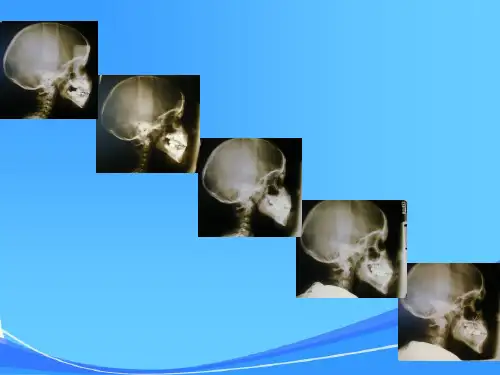

在人类的整个生命周期中,颅面部的生长发育一直在进行,从出生时到成年后,颅面部的形态和结构都会发生显著的变化。

5. 面部比例的变化:随着年龄的增长,颅面部的比例会发生变化。

在婴幼儿期,颅骨相对较大,面部相对较小,随着年龄的增长,面部逐渐发育,与颅骨的比例逐渐接近成人。

颅面部生长发育的完成顺序面部的生长发育初生时面部以宽度为最大,但出生后的增长以高度为最大,深度次之,宽度又次之。

总的来看是头颅完成后,按面部的宽度、长度和深度的顺序而完成。